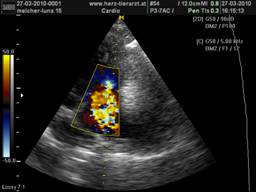

Der Herz-Ultraschall ist gerade in der Tiermedizin die zuverlässigste und aussagekräftigste Methode der Kardio-Diagnostik. Im Gegensatz zum Röntgen, welches nur die äußere Größe der Herzsilhouette beschreiben kann, ist es mit dem Ultraschall möglich zu unterscheiden, ob eine Herzvergrößerung durch eine krankhafte Muskelverdickung oder aber durch eine Herzüberdehnung bedingt ist. Der Ultraschall ermöglicht uns außerdem, direkt ins Innere des Organs zu blicken und jede einzelne der insgesamt vier Herzklappen darzustellen, sodass Klappen –Verengungen und –Verdickungen sowie undichte Klappen eindeutig erkennbar sind, was von enormer Wichtigkeit für die Wahl des richtigen Medikaments ist. Mit der hochmodernen Doppler-Sonographie werden schließlich noch die Stärken der einzelnen Blutströmungen gemessen, was für die endgültige Diagnose und für spätere Kontrollen von Bedeutung ist, um den Verlauf der Krankheit und den Therapie-Erfolg zu beurteilen.

Obwohl der Herz-Ultraschall die mit Abstand beste Untersuchung vom Herzen ermöglicht und beliebig oft wiederholbar ist, ohne den Patienten einer Strahlenbelastung auszusetzen, bleibt sie aufgrund der hohen Geräte-Anschaffungskosten und der nötigen jahrelangen Erfahrung des Untersuchers nur wenigen Spezialisten vorbehalten. |